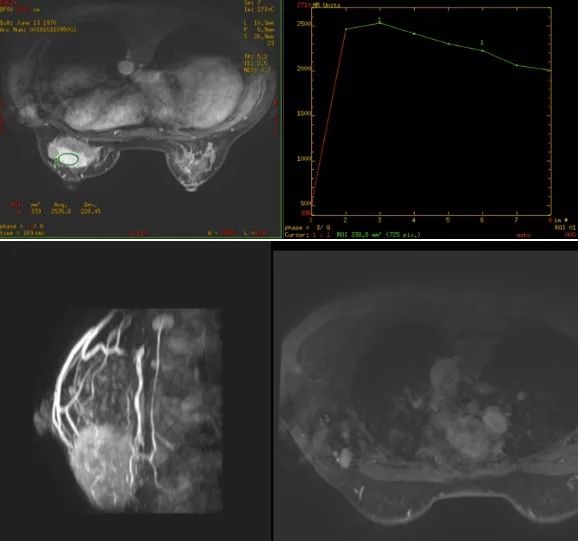

肿块明显缩小,皮肤受侵,但无破溃迹象。乳腺超声(2019年3月4日):左乳癌新辅助化疗后未见明确肿物。乳腺钼钯(2019年3月4日):未见明确肿物。乳腺MRI:左乳下象限肿块较前明显缩小,左腋窝多发淋巴结较前减小。疗效评价部分缓解(partial response,PR)。

乳腺MRI